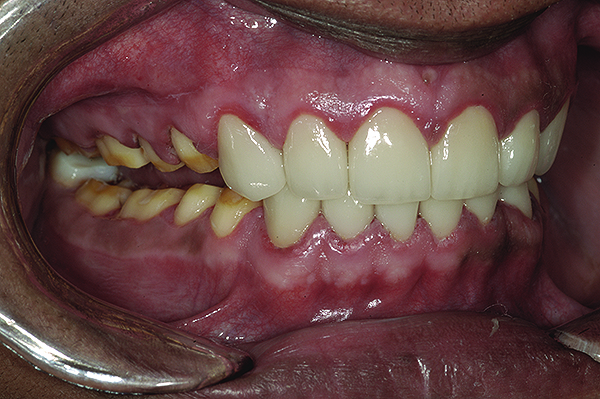

Figure 2. Preoperative 1:2 retracted frontal view.

Figure 2

Figure 3. Preoperative 1:2 retracted right lateral view.

Figure 3

Figure 4. Preoperative 1:2 retracted left lateral view.

Figure 4

Figure 5. Preoperative 1:1 retracted frontal view.

Figure 5

A thorough clinical examination and analysis were carried out to assess the esthetic and functional problems of the patient (Figure 2 through Figure 7). The medical history was non-contributory, except for mild leukoderma. Temporomandibular joint (TMJ) function was within normal range.